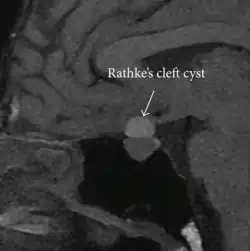

| Rathke's cleft cyst in a 53-year-old man with a pituitary adenoma and acromegaly |

A Rathke's cleft cyst is a benign growth on the pituitary gland in the brain, specifically a mucin-filled[1] cyst in the posterior portion of the anterior pituitary gland.[2][3] It occurs when the Rathke's pouch does not develop properly and ranges in size from 2 to 40 mm in diameter.[3]